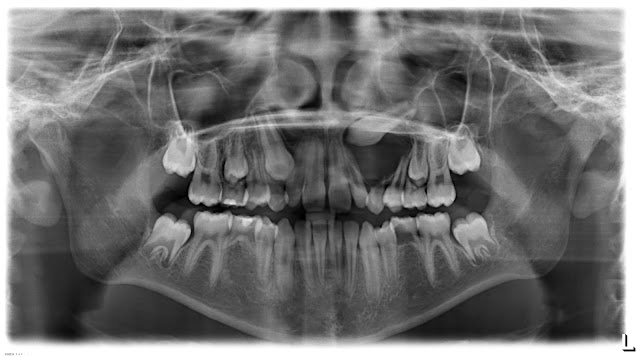

Ragazza di 12 anni |

Anomalia di numero |